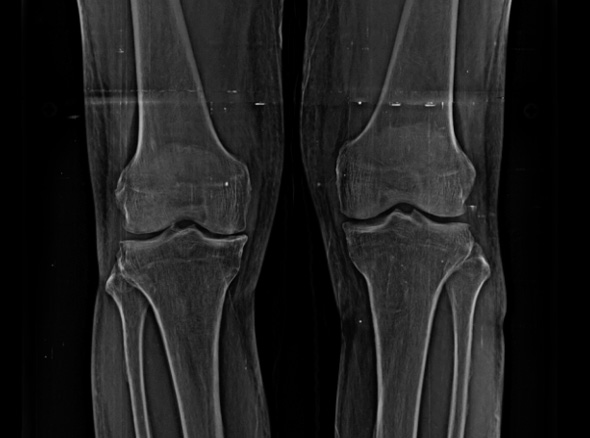

퇴행성관절염은 치료의 시기가 매우 중요합니다.

한번 진행이 시작되면 피하기가 어려워 치료가 빠를수록 진행을 최대한 늦출 수 있습니다.

초기에는 수술이 아닌 비수술 치료만으로 생활에 불편함이 없도록

통증을 완화시키고 증상을 충분히 완화시킬 수 있습니다.

중기에는 비수술치료를 진행하고, 증상이 악화되는 경우 정상 조직을 최대한 보존하고 병변부위만 선택적으로 수술하는 관절내시경을 진행하게 됩니다.